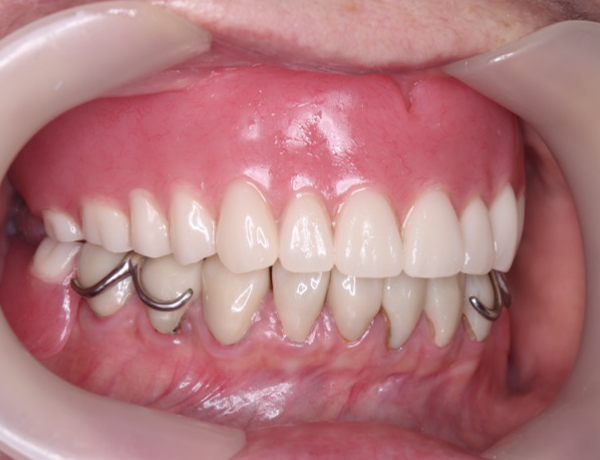

正面観

左下に入れ歯が入っておらず歯がないので、噛み合わせは左右アンバランスになってますね。赤丸の部分は、骨隆起ですね!噛み合わせの強い方に現れる骨の隆起になります。